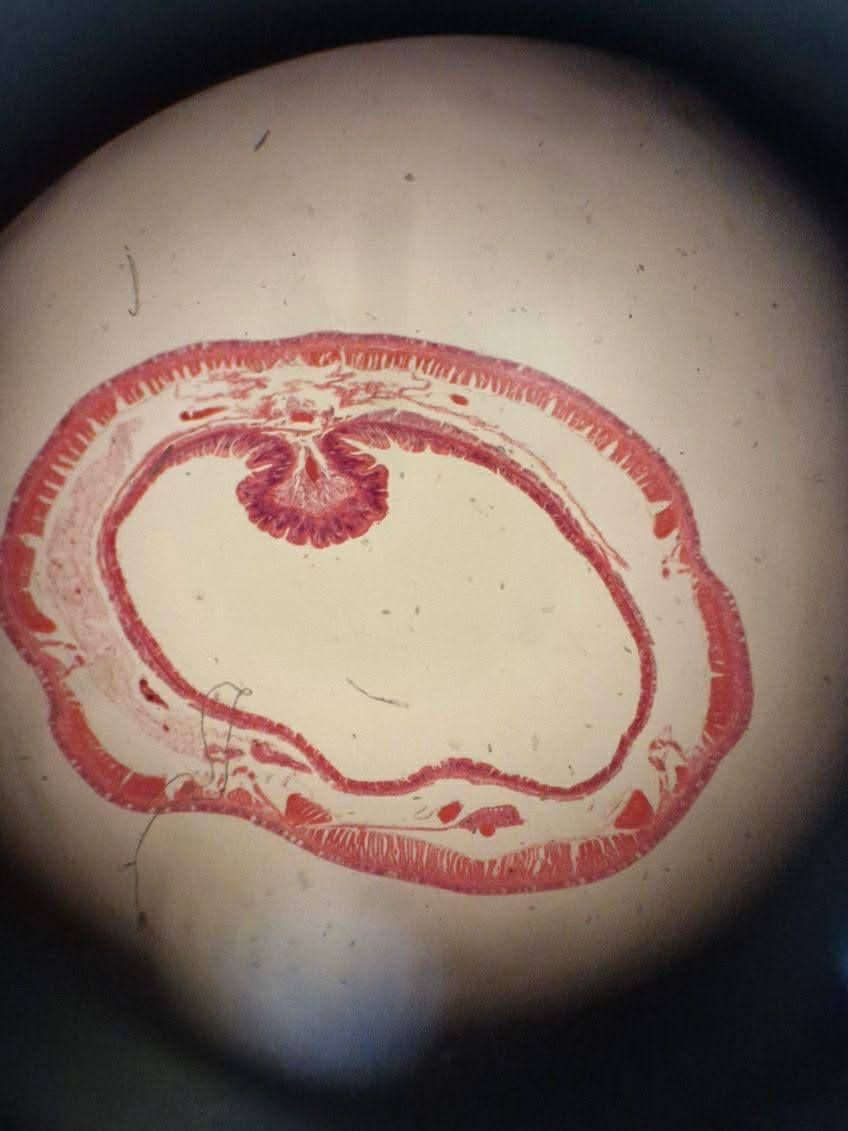

Dzieci samodzielnie przygotowywały preparaty, obserwowały je pod mikroskopem i odkrywały, jak wiele ciekawostek kryje się w kropli wody czy fragmencie liścia.